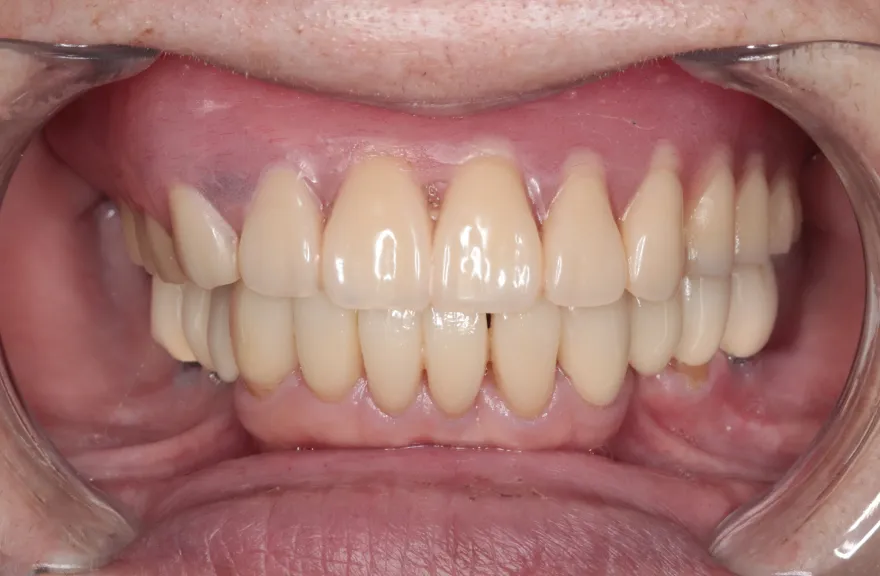

既にインプラント治療がなされており、使えるインプラントを使いながら足りないところにインプラントフィクスチャーを埋入し、噛み合わせを再構築する必要がある方でした。

上の前歯、右上の奥歯のインプラントはもう既に使える状態ではなく、また年月を経てすり減ってしまった下の前歯は噛み合わせを再構築する上で利用が難しい状況でした。

年齢を考えると、今回の治療で歯科治療を終えてしまい、残りの人生においてはメンテナンスのみで歯科へ通う状況を作りきってしまうことが求められました。

以上より、潔く残っている歯牙は抜去させていただき、上下をインプラントフィクスチャーによって固定式の歯を入れることとしました。 - 治療のリスク